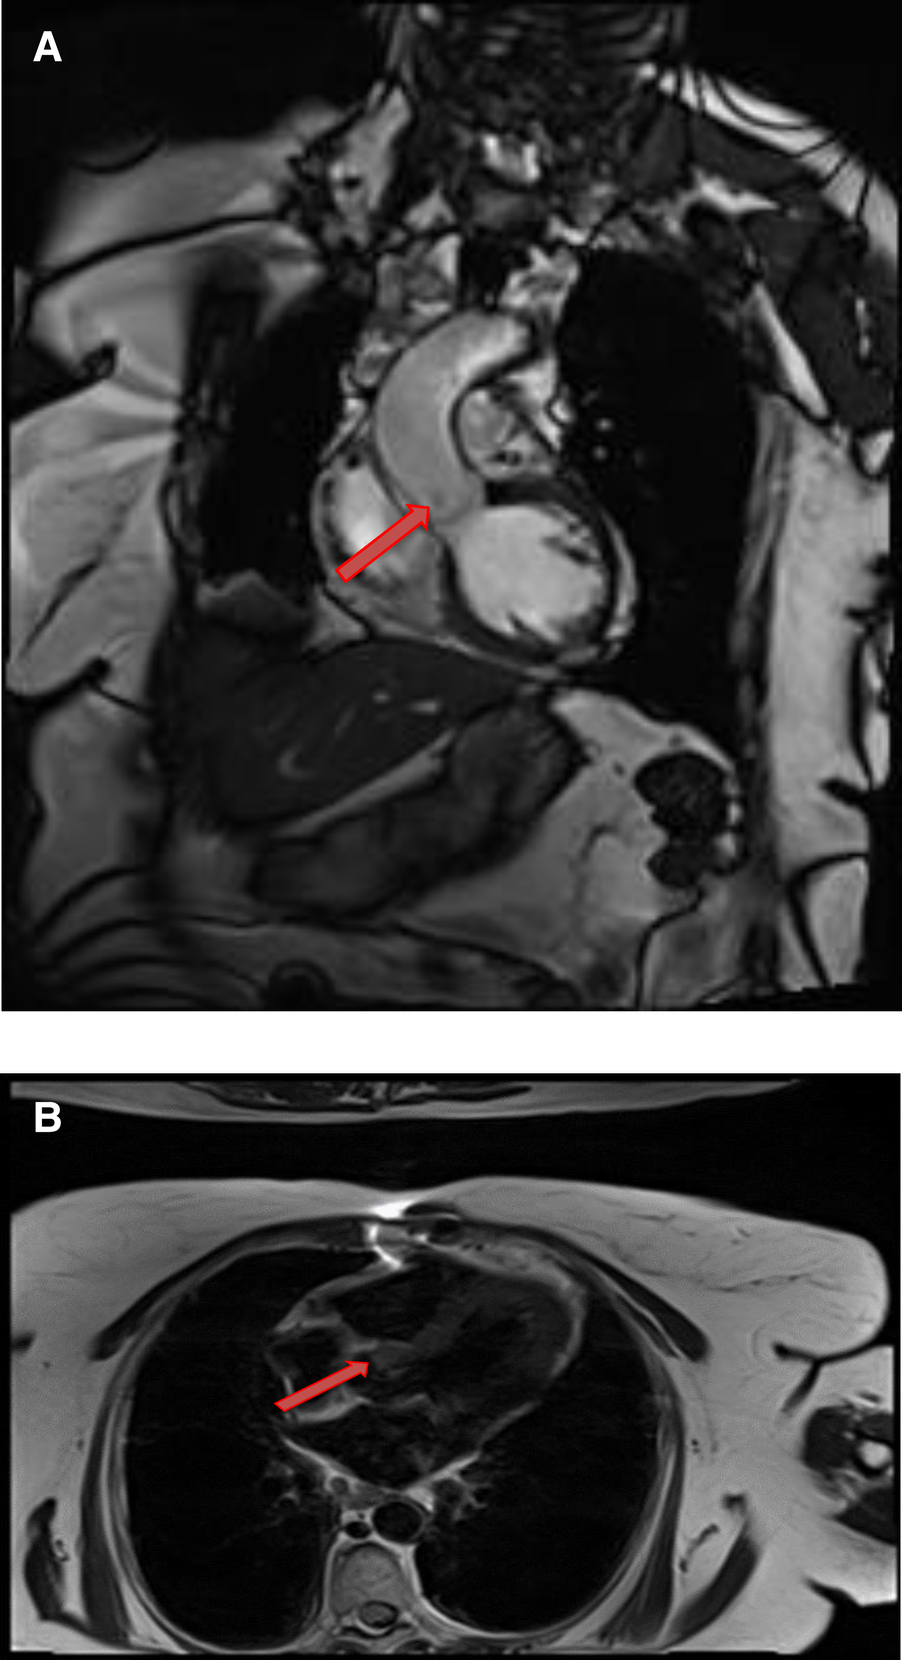

Figure 10

A 31-year-old male with left ventricular fibroma. (A) This mass demonstrates no perfusion on first-pass imaging (red arrow, short axis view). (B–F) Homogeneous intense enhancement of the mass is noted on late gadolinium enhanced images (red arrows, 3chamber and short axis views).

4.5.1. Cardiac MRI features

Fibromas are of variable signal intensity on SSFP cine images. As compared to the myocardium, they are usually isointense on T1-weighted images and are characteristically hypointense on T2-weighted images (50). Although, they are generally homogeneous in appearance, a patchy, central hypo intensity may be seen due to central calcification, which gives them a heterogeneous appearance.

They are avascular in nature and do not show contrast enhancement during perfusion imaging. Characteristically, they show intense hyper-enhancement on LGE images. The potential explanation of this intense LGE pattern is that microscopically they are composed of collagen and fibroblasts; therefore, they have a very large extracellular space content. Gadolinium diffuses into interstitial spaces and results in a delayed and persistent concentration of gadolinium contrast agent (Table 1 and Figure 10).

Figure 11

A 54-year-old male with right ventricular pheochromocytoma. (A) The mass is isointense on T1- weighted, dark blood, double inversion recovery fast spin echo images (red arrow). (B) The mass demonstrates peripheral hyper-vascularity with central areas of nonenhancement on first pass perfusion images (red arrow). (C) There is central enhancement of this mass on late gadolinium enhanced images (red arrow).

Figure 12

A 53-year-old male with inter-atrial septal pheochromocytoma. (A) The mass is bright on T2- weighted, dark blood, double inversion recovery fast spin echo images (red arrow). (B) This mass shows heterogeneous enhancement on late gadolinium enhanced images (red arrow).